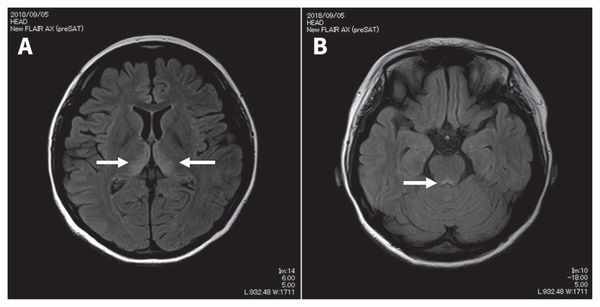

Перивентрикулярная лейкомаляция у недоношенного рожденного на 25 неделе гестации девятилетнего мальчика.

Аксиальная МРТ, видны множественные мелкие высокоинтенсивные фокусы в режиме FLAIR в перивентрикулярном и субкортикальном белом веществе, представляющие собой ишемические изменения или глиоз.

Отмечается значительное расширение желудочков с утратой прилегающего белого вещества.